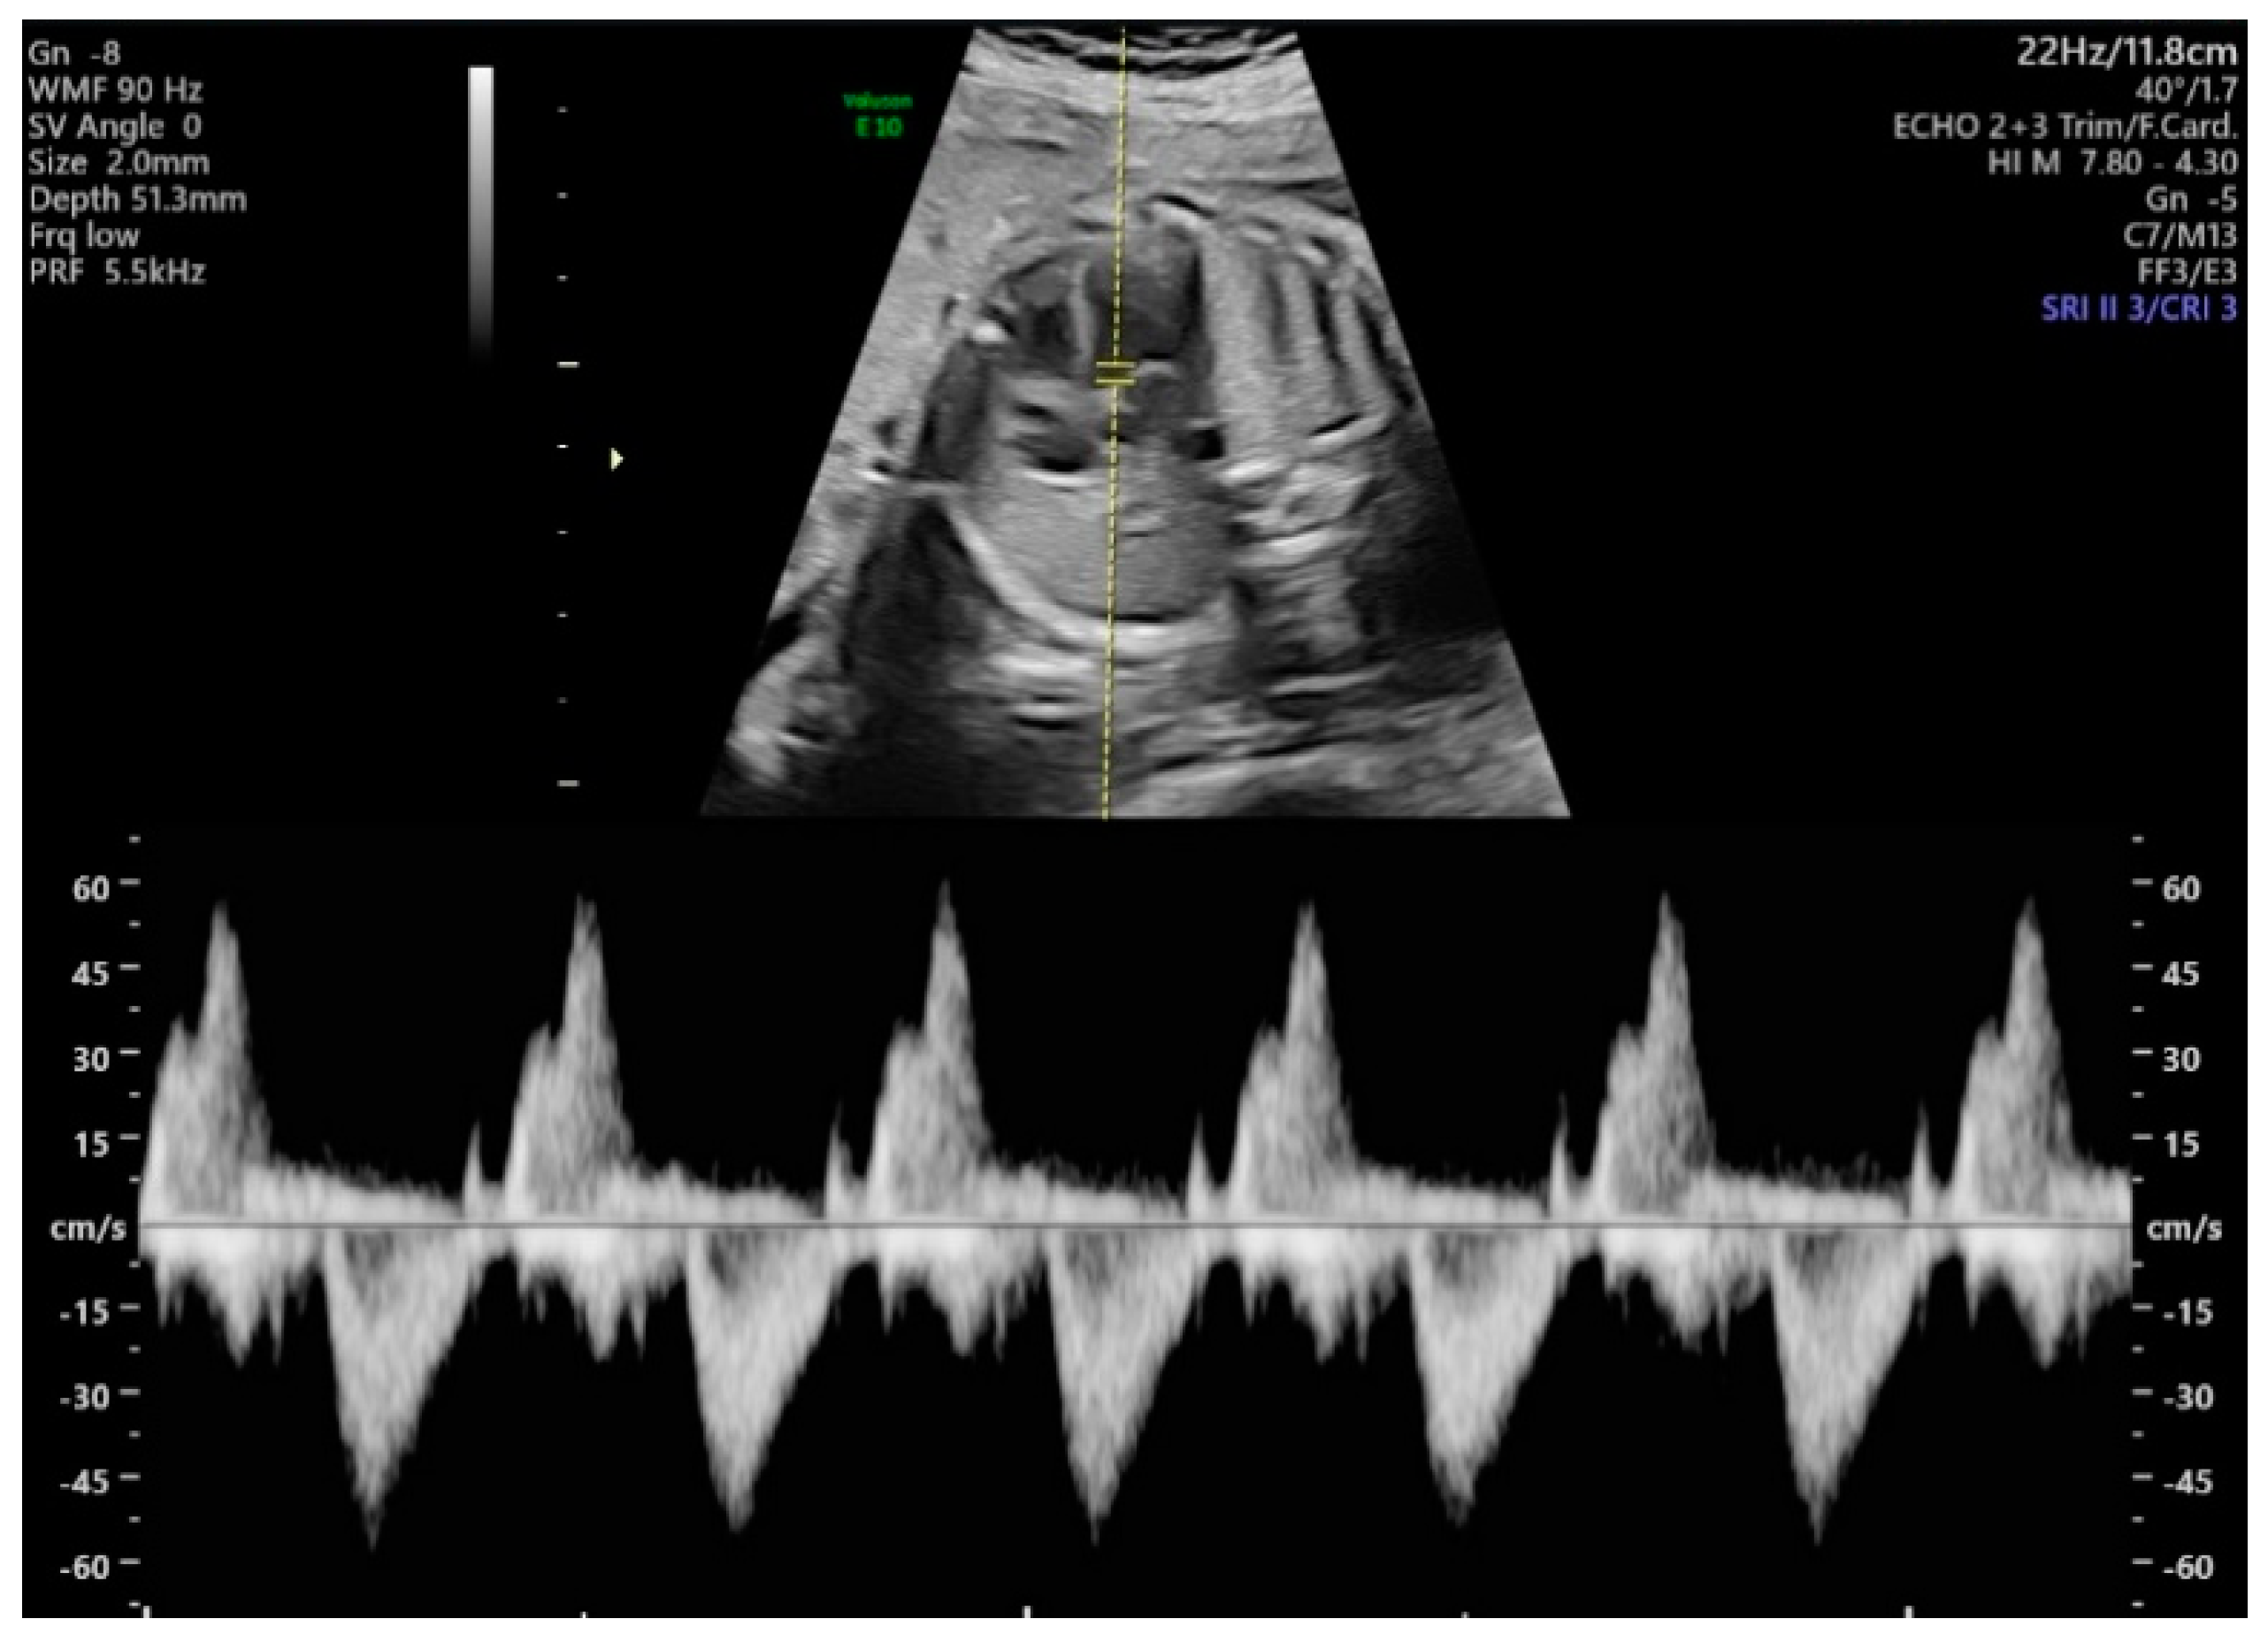

The methods used for acquiring Doppler waveforms for measuring the MPI were as follows. First, the aortic cortical part of the fetus was checked by turning the probe slightly in the direction of the fetus’ shoulder in the apical four-chamber view. Next, the pulse Doppler mode was executed, the sample volumes were positioned close to the aorta and the mitral valve, and the blood flow waveforms were obtained. Using the invert function during the examination, we set the left ventricle inflow blood flow to positive and the outflow blood flow to negative; the sweep speed was set to 5, and the sample volume size was fixed at 2 mm. Other ultrasound settings included low Doppler gain, 60 Hz wall motion filter, 8.3 kHz PRF (pulse repetition frequency), less than 0.4 thermal index and less than 0.7 mechanical index, and angle of insonation less than 20. The equipment used was a Voluson E10 ultrasound machine (GE Healthcare, Chicago, IL, USA) with a 3.5 MHz convex array probe (C2-D). The two-dimensional (2D) images and Doppler waveforms of the measurements are shown in Figure 1, including more than 4 cycles per fetus. During the examination, one operator performed a measurement of time intervals at the same time and stored both manual and original images. Automatic measurements were made on stored images. To assess intraoperator variability, we took measurements again by the same operator on a different time.

Figure 1. Two-dimensional (2D) images and Doppler waveforms of the measurements.